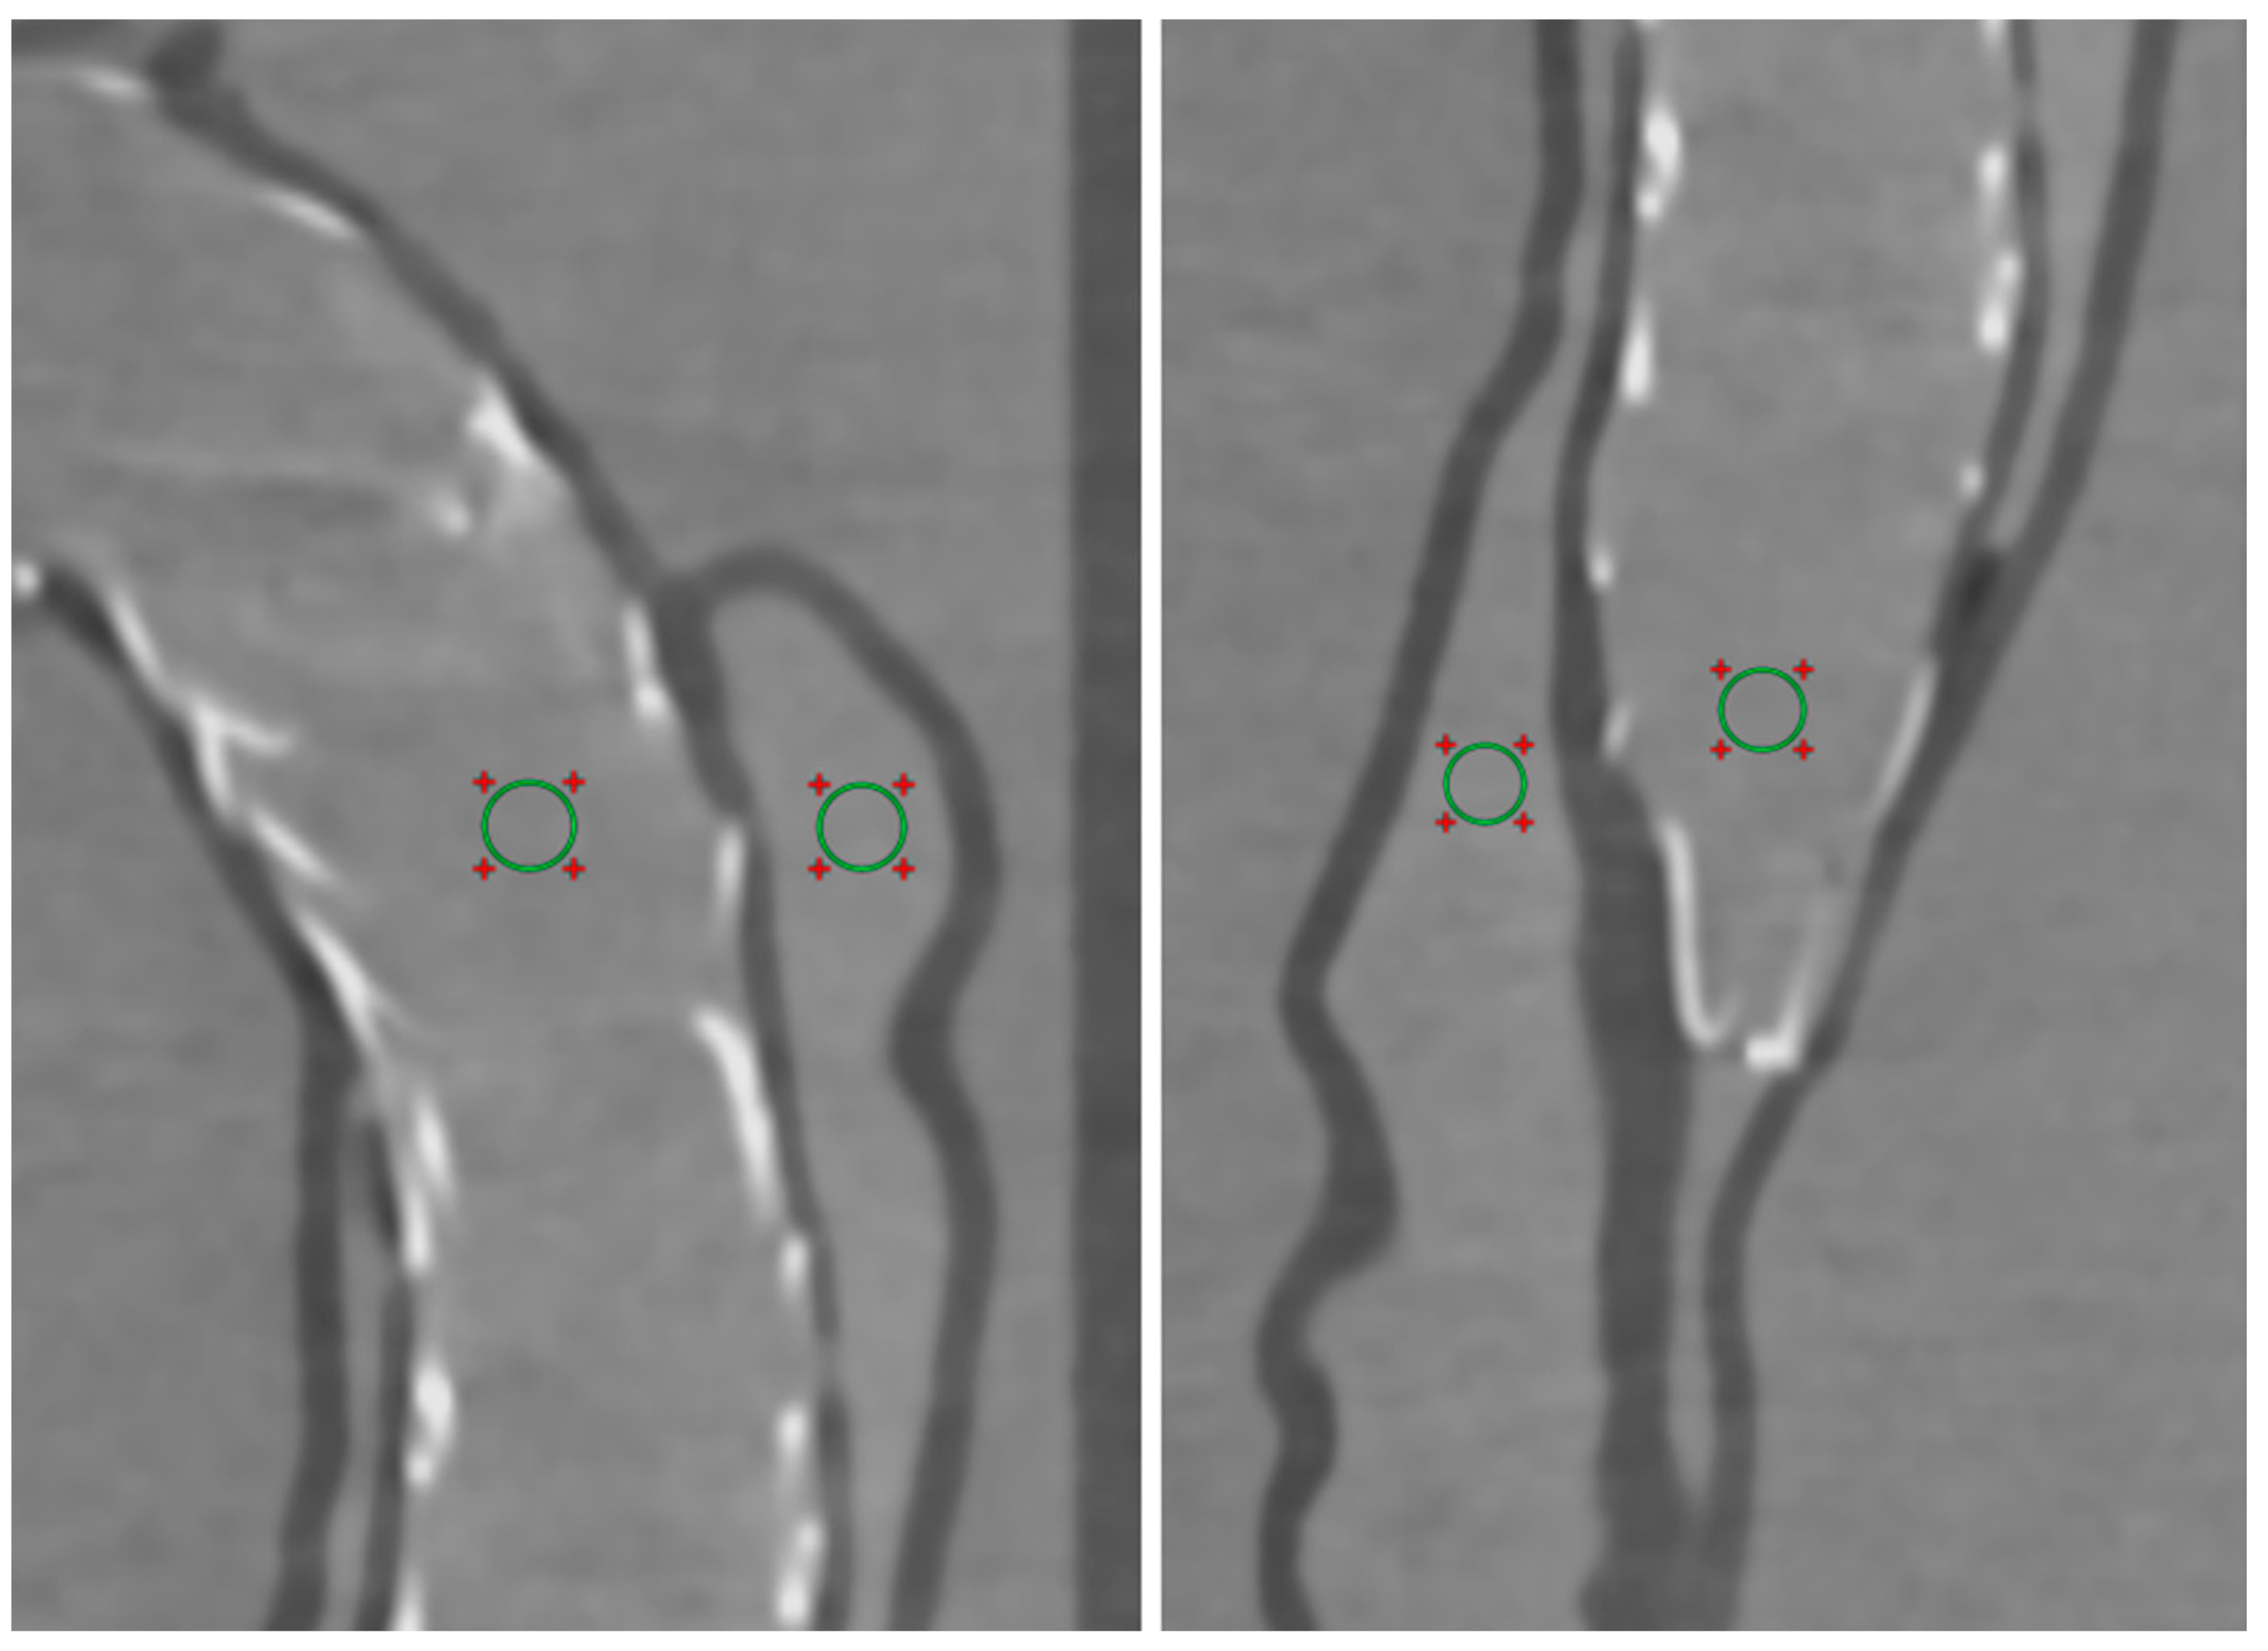

2.5. Quantitative Assessment of Image Quality